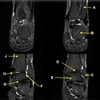

INFRASPINATUS MUSCLE

How well did you know this?

1

Not at all

2

3

4

5

Perfectly

10

Q

What is letter D?

A

GLENOID